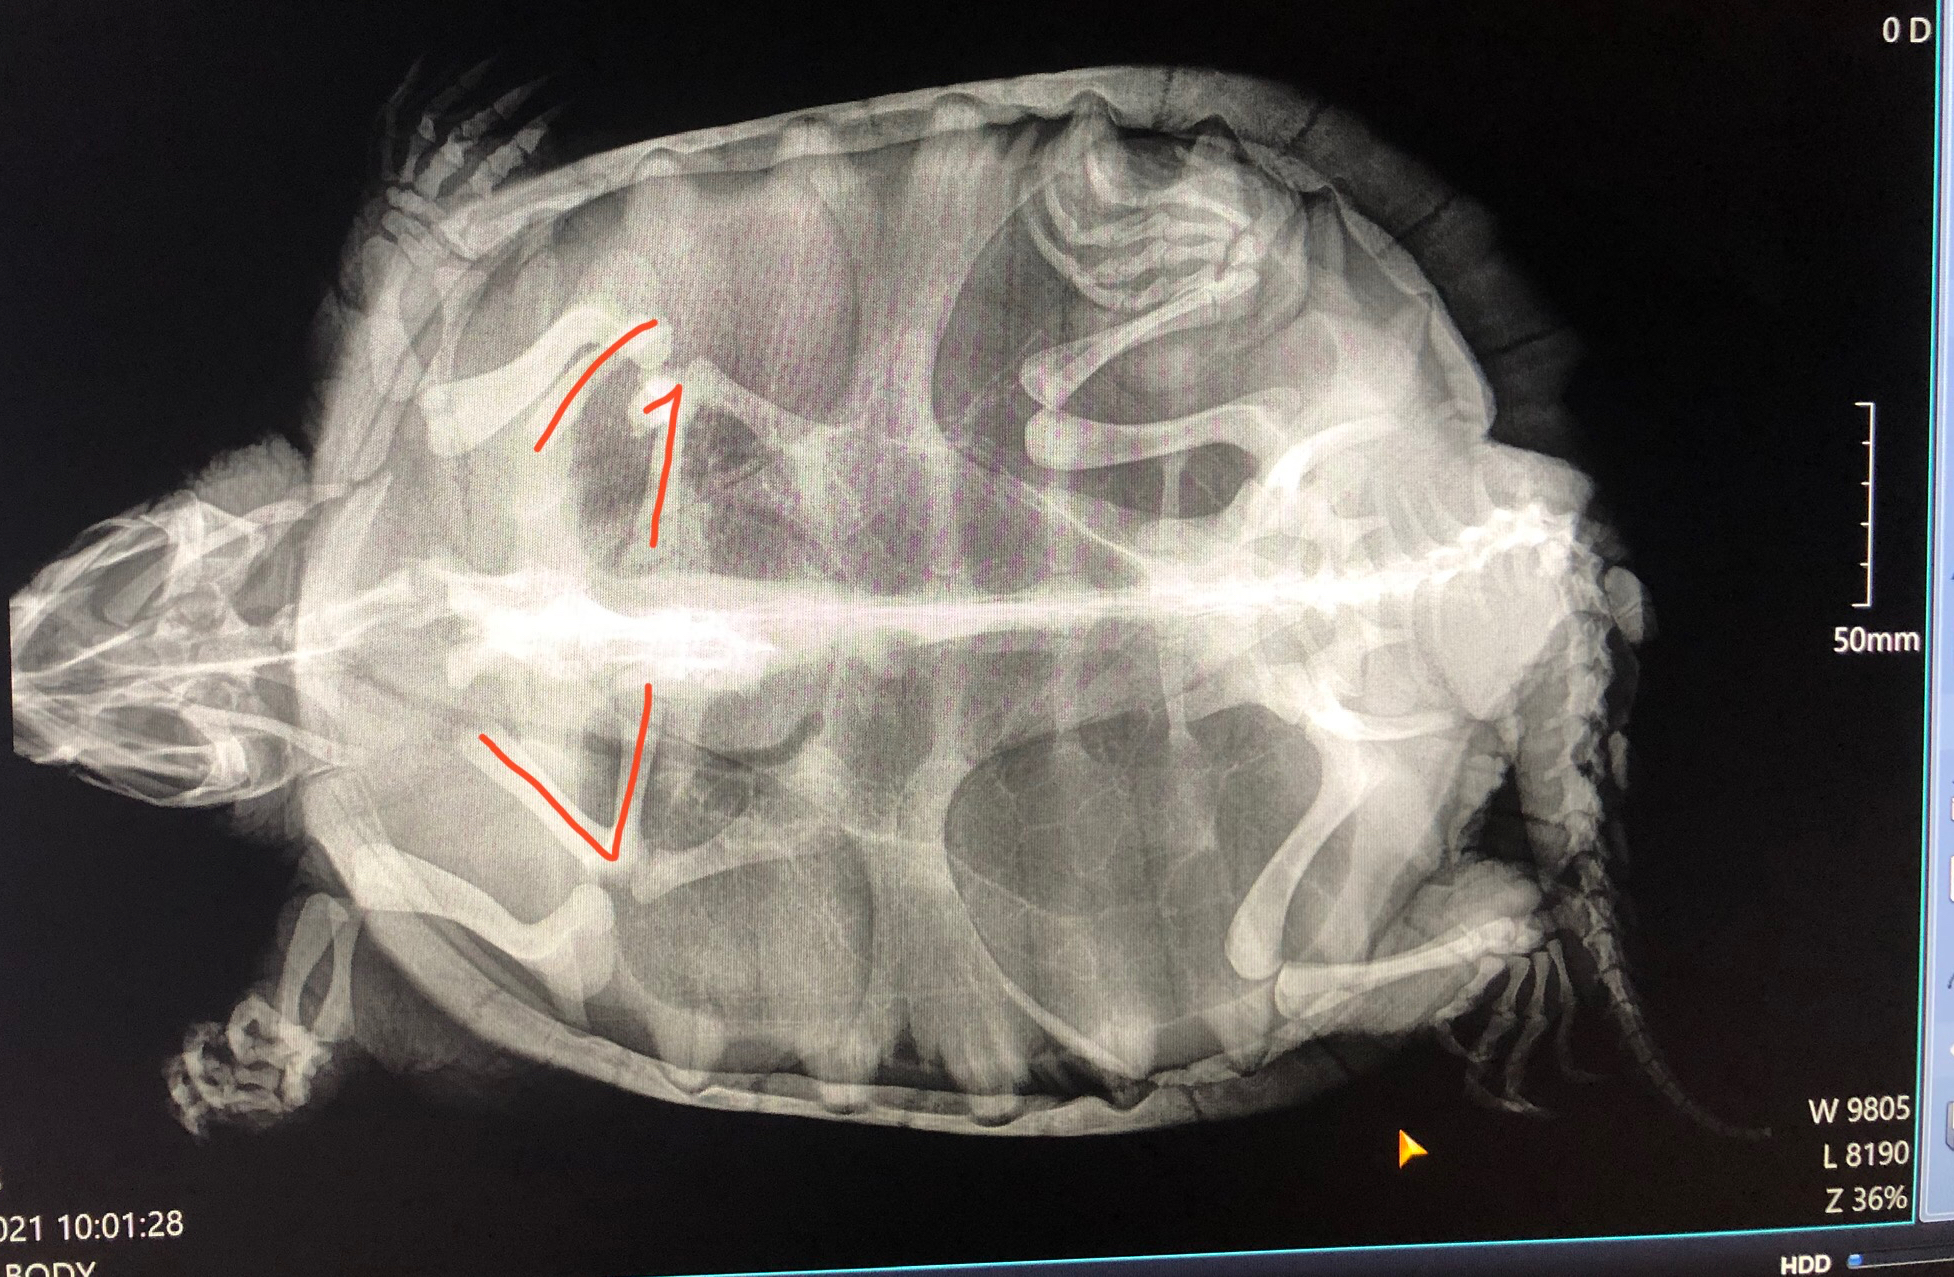

More time passes, and he starts going downhill, despite parts of his shell starting to heal. Claude Magnus starts getting slow, not showing interest in food, not even trying to snap at me when I pick him up. I examine him more closely and it appears he isn’t snapping anymore because he physically can’t. I bring him to the vet for x-rays and discover he has a broken and very dislocated collarbone.

Now, turtles are pretty tough and just falling shouldn’t have broken his bone. It’s likely that it was broken by the car that hit him, but that his constant escape attempts and landing directly on the fracture pushed it out of position. I consulted three different vets who all basically told me the same thing. “There’s not much hope for him.”

A snapping turtle who can’t extend his neck because a dislocated and fractured bone is in the way, who has decreasing strength in one arm and lowered ability to swim, who can’t even open his mouth all the way anymore, isn’t going to survive in the wild. The poor thing couldn’t eat on his own and it was unlikely even surgery would be enough to fix his internal injuries. Keeping him alive by force-feeding him and in shallow water because he couldn’t extend his neck very far nor swim very well in order to breathe is no way for this majestic dinosaur to live out the next 6 or 7 decades of his natural life.